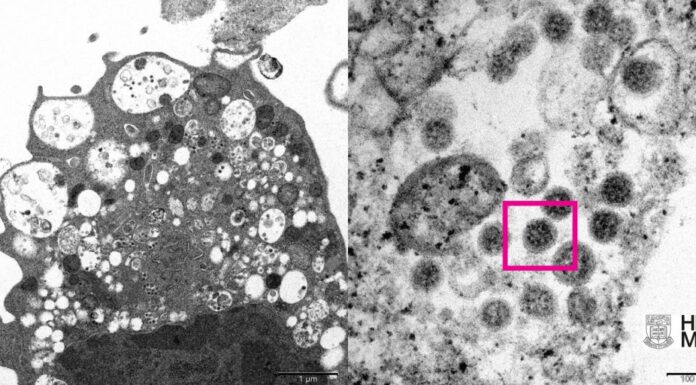

Reprodução / Faculdade de Medicina da Universidade de Hong KongVariante ômicron se tornou a prevalente em todos...